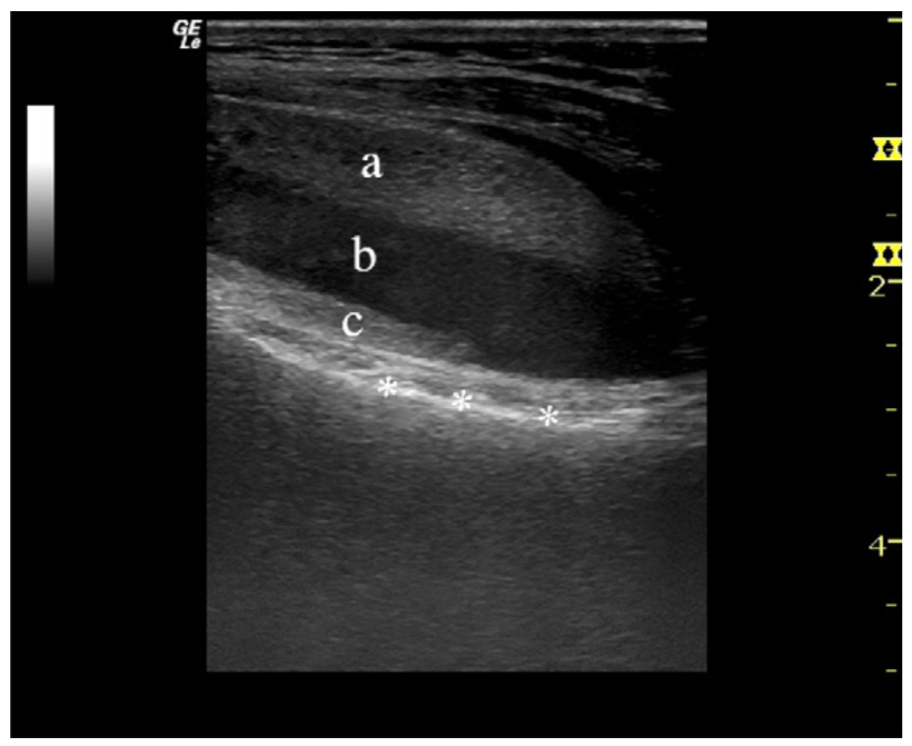

发生关节囊内骨折后,从骨髓腔或撕裂的骨膜处溢出的脂肪组织和血液同时进入关节腔内。由于血液密度相对较大,沉于关节液之下,而脂肪密度相对小,漂浮于关节液之上,从而形成分层现象。关节积脂血症液体分层从上到下依次为:脂肪、关节炎、血液。

在X线、CT、MR及超声检查中均可发现积脂血症。

膝关节骨折较为常见,且膝关节腔及髌上囊较大,液体分层通常较其余关节更易发现。